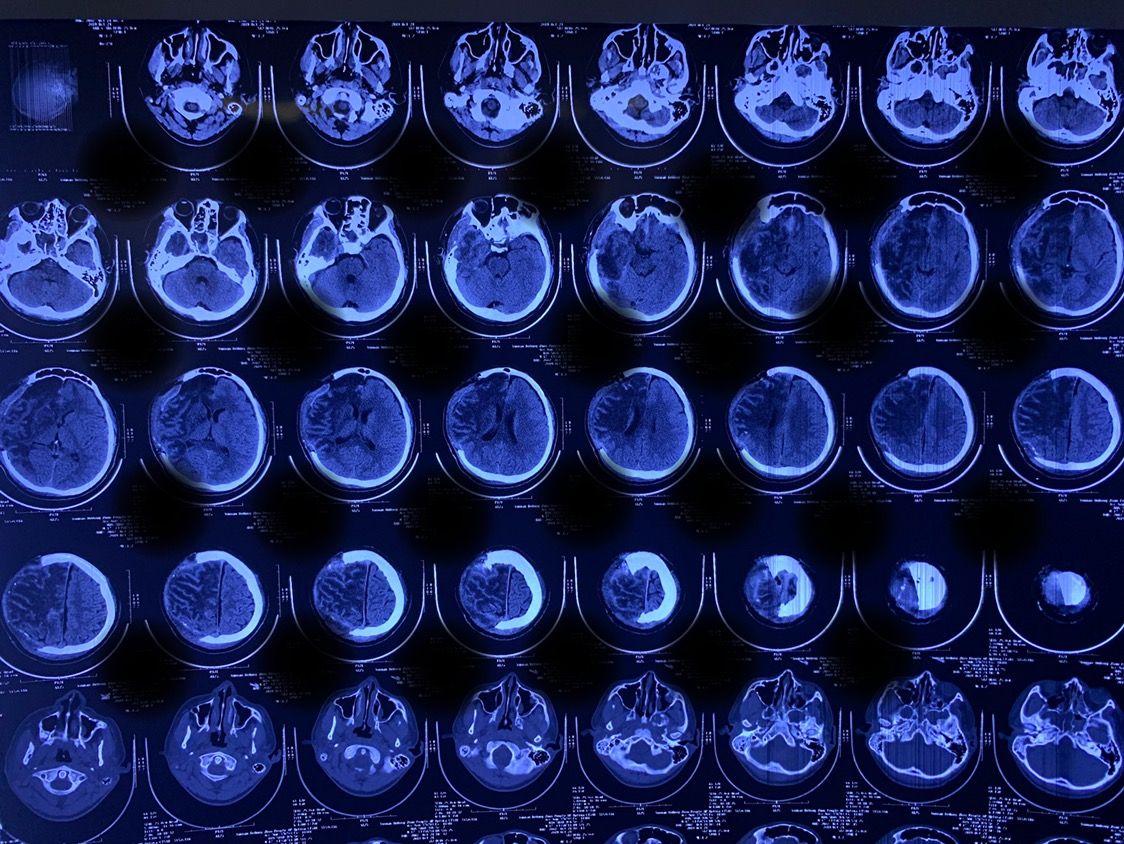

术后复查CT

目前患者一般情况良好,意识清醒,认知障碍较前明显好转,能简单交流。左侧肢体肌张力较前明显下降。在家属搀扶下能行走。